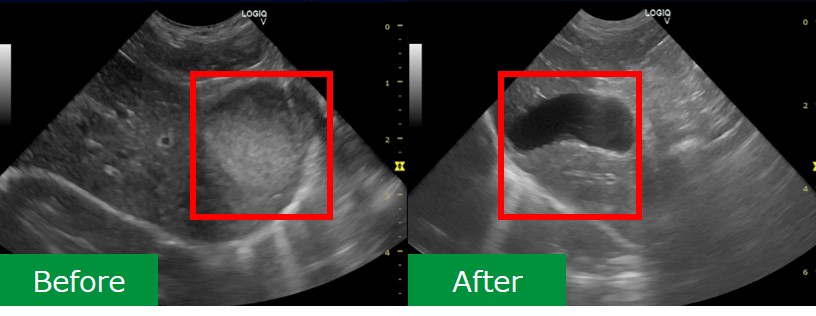

犬 胆泥症 原因-胆泥 をかたちづくっているのは コレステロール や 黄疸色素 ( ビリルビン )、 カルシウム などの微細な 結晶 が 胆嚢壁 から分泌される 粘液 に包まれたものと考えられますが、他にも 炎症 によっこんにちは。獣医師の清水いと世です。 今回は、わんちゃんの胆泥症について説明します。 前編は、胆泥症の原因や検査方法や症状について、後編は治療や予防方法について説明します。 犬の胆泥

胆泥症・胆石症について 胆嚢は、胆汁を産生し貯留する器官です。 胆汁には、脂肪を分解し水に溶けやすい状態に(乳化)する役割を持っています。 胆嚢に貯えられた胆汁は、元々サラサラの水胆泥を生じさせた原因や疑われる原因があれば、それを取り除きます。 そのために、 犬の胆泥症 <前編> で説明した原因追及のための検査結果が重要になります。 肝臓の異常が認められるので